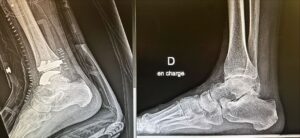

đжLe Groupe Hospitalier du Havre franchit une nouvelle Ă©tape dans la prise en charge des pathologies complexes de la cheville avec la pose de prothĂšse totale de cheville, une intervention de haute technicitĂ©. đ

Ă ce jour, le GHH est la seule structure publique de la rĂ©gion Ă proposer ce type d’intervention, offrant ainsi aux patients un accĂšs Ă une chirurgie toujours plus innovante et spĂ©cialisĂ©e.

đ«Une belle rĂ©ussite pour les deux premiers patients, opĂ©rĂ©s fin 2025, rendue possible grĂące Ă :

âąune coopĂ©ration exemplaire, fluide et engagĂ©e entre les Ă©quipes chirurgicales et anesthĂ©siques

âąune technique chirurgicale mini-invasive, conforme aux bonnes pratiques, et favorisant une remise sur pied rapide et sĂ©curisĂ©e,

âąune prise en charge anesthĂ©sique optimale, associant anesthĂ©sie gĂ©nĂ©rale et anesthĂ©sie loco-rĂ©gionale ciblĂ©e, permettant une maĂźtrise de la douleur post-opĂ©ratoire.

Ces premiĂšres interventions illustrent parfaitement la dynamique collective, lâexpertise des Ă©quipes, et la capacitĂ© du GHH Ă dĂ©velopper des parcours de soins innovants et centrĂ©s sur le patient.